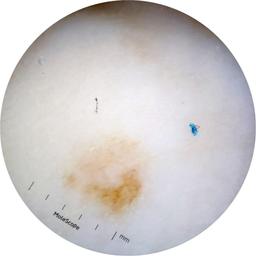

ISIC_2631400

MEL-SELF Trial, https://www.sydney.edu.au/medicine-health/our-research/research-centres/melself-project.html

Clinical

Field Value

acquisition_day 146

age_approx 70

anatom_site_1 Lower extremity

anatom_site_general lower extremity

concomitant_biopsy False

diagnosis_1 Benign

diagnosis_confirm_type single image expert consensus

family_hx_mm True

fitzpatrick_skin_type I

image_manipulation instrument only

image_type dermoscopic

lesion_id IL_2672529

patient_id IP_8223109

personal_hx_mm True

sex female